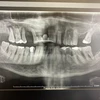

Diş Eksikliği

Periimplantitis

Peri-İmplant Mukozitis

Implant tedavisi